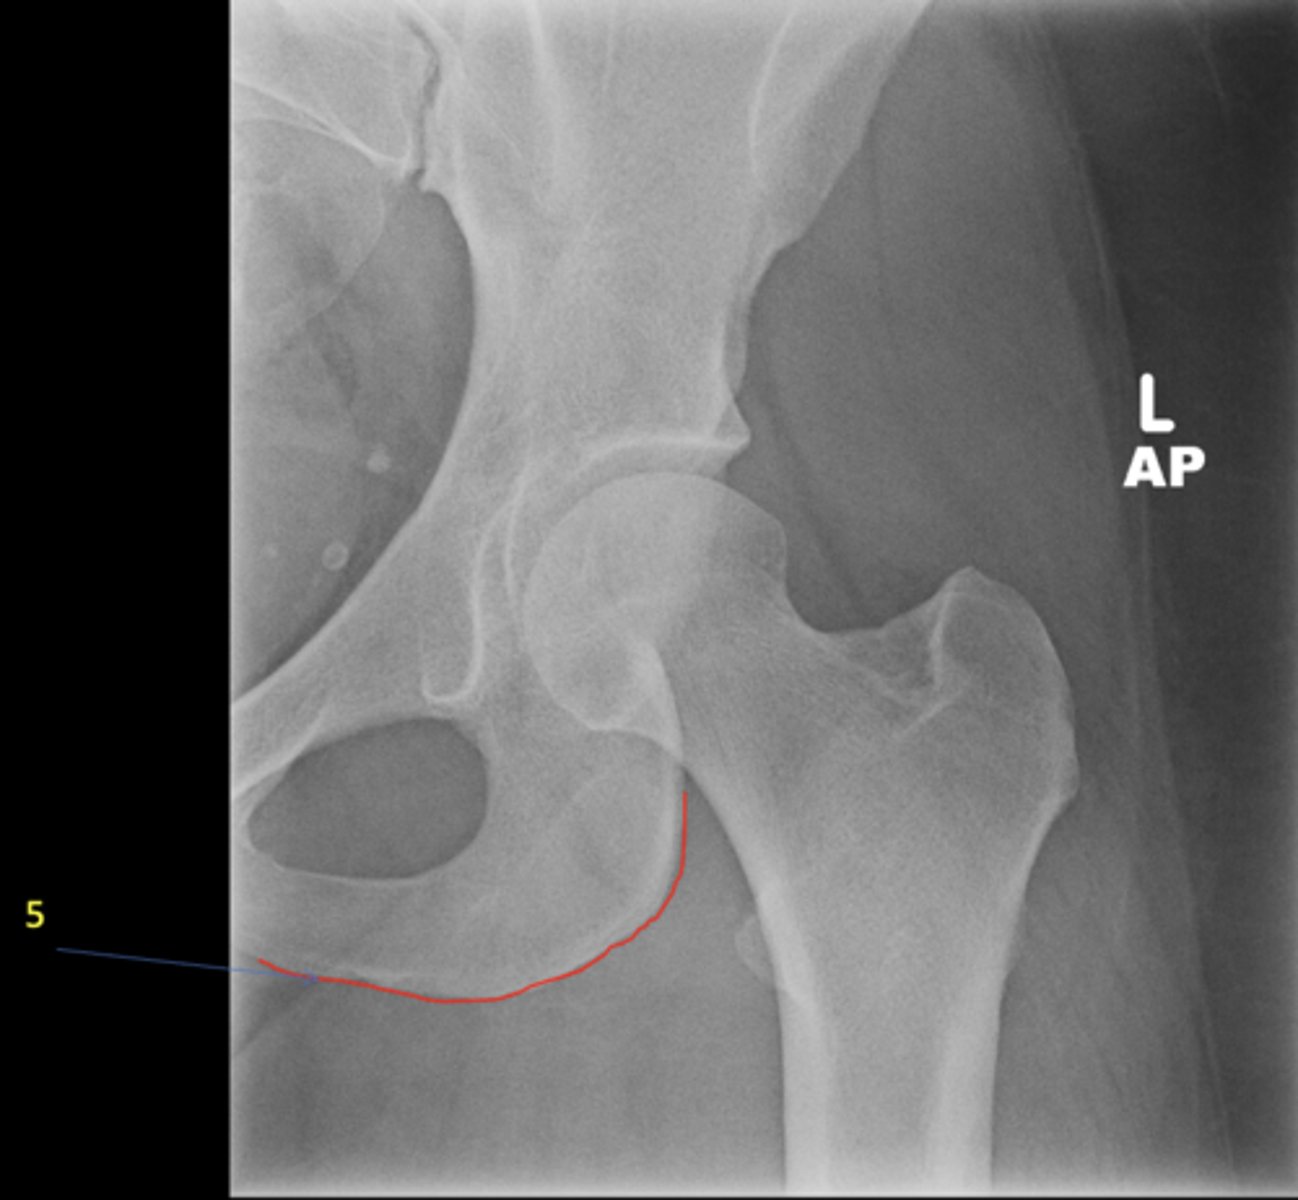

<p>View?</p>

5

New cards

Right iliac fossa

ID 5

<p>ID 5</p>